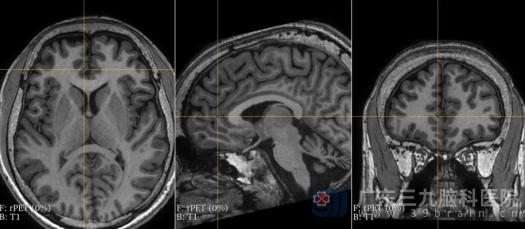

图4

视频脑电图上机2天,提示患者发作间期右侧后头部和前头部有癫痫样放电,无减药诱发发作下共记录到10次,每次发作均有“军帽征”表情(扁嘴、痛苦表情)→床上左右滚动、口中发出无意识“啊啊”声,同步记录心电图课件心率增快(植物神经症状),随后发展为全身抽搐(GTCS),左侧肢体症状为著。MRI检查虽未发现明显异常,但PET检查提示右侧前扣带回、右侧颞-岛叶、右颞底面低代谢(图1~4)。同时,智力测试结果显示,患者的全量表智商(FIQ)为62,言语智商(VIQ)为66,操作智商(PIQ)为62,记忆商数(MQ)低于51,这表明癫痫对他的智力造成了严重影响。